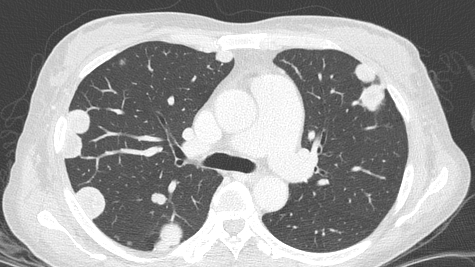

Обнаружение очагов в лёгких при прохождении КТ ОГК – тревожный диагноз, который вызывает много вопросов и беспокойства. Такие образования могут появляться по разным причинам: от безобидных последствий перенесенных инфекций до серьёзных заболеваний. Важно понимать, что наличие очагов не всегда означает «онкологию», но в любом случае требует внимательного обследования и консультации со специалистом. В этой статье мы разберем возможные причины таких изменений, методы диагностики и дальнейшие шаги, если у вас обнаружены очаговые изменения в лёгких...

Согласно исследованиям регистра пациентов с идиопатическим легочным фиброзом (ИЛФ), в России фиброз легких встречается у 4–7 человек из 100 000. В статье рассказываем о видах, причинах возникновения и симптомах фиброза легких, а также о методах диагностики и лечения этого заболевания. Фиброз легких — это необратимый процесс замещения здоровой ткани легких рубцовой, в результате чего снижается эластичность легких. Так, альвеолы (легочные пузырьки, в которых происходит газообмен) теряют способность нормально расширяться и сокращаться...